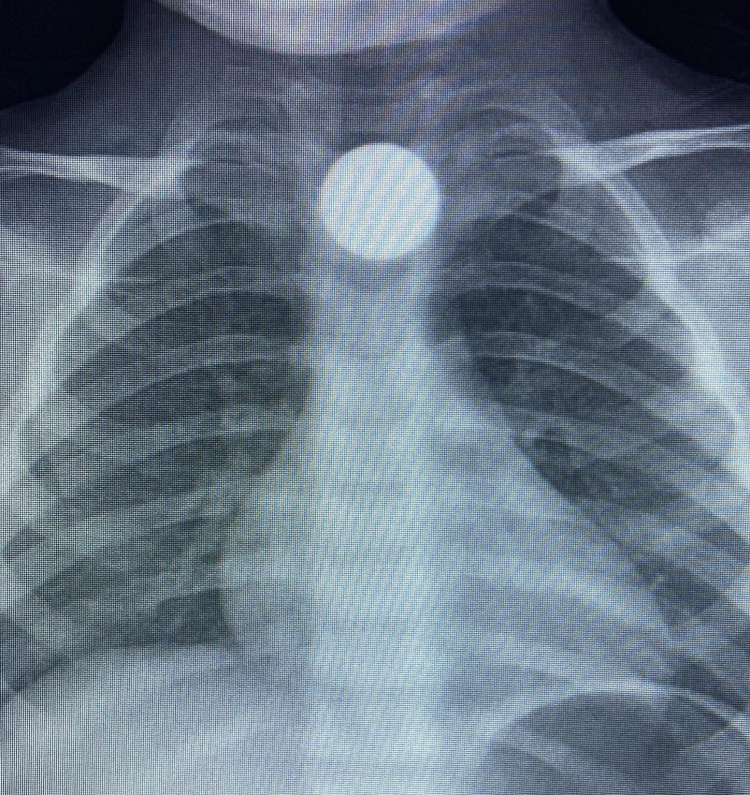

3 yaşındaki Bilal K., evde yerde bulduğu 50 kuruş madeni parayı ağzına atıp yuttu. Olayı fark eden ailesi tarafından çocuk özel araçla İnegöl Devlet Hastanesi'ne kaldırıldı. Yapılan tetkiklerde yemek borusunda takılı kalan madeni para görüldü. Çocuk ilk tedavinin ardından ambulansla Bursa Yüksek İhtisas Eğitim Ve Araştırma Hastanesi'ne sevk edildi.